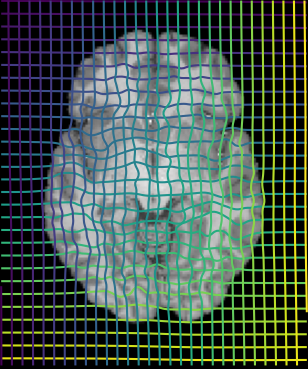

Inverse consistent rigid, affine, nonparametric, and MLP registration. We train networks on MNIST 5s using the methods in Secs. 3 and 4, demonstrating that the resulting networks are inverse-consistent. Our TwoStepConsistent (TSC) operator can be used on any combination of the networks defined in Sec. 3. For demonstrations, we join an MLP registration network to a vector field registration network, and join two affine networks to two vector field networks. Fig. 2 shows successful inverse-consistent sample registrations.

| Moving Image | Warped Image | Fixed Image | Moving Image | Warped Image | Fixed Image |